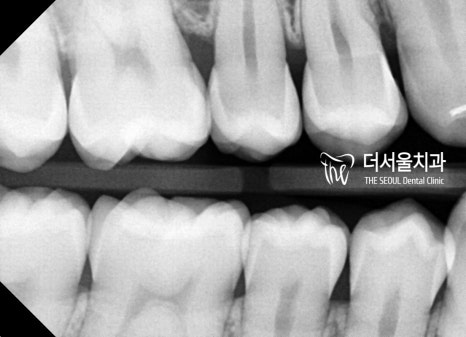

【 마무리 】

모든 치료가 마무리된 모습을 살펴볼까요?

이전과는 달리 훨씬 안정적인 모습의

맞물림이 관찰되고 있습니다.

교합은 물론이며 더욱 긴밀한 배열을

갖게 된 것을 볼 수 있는데요.